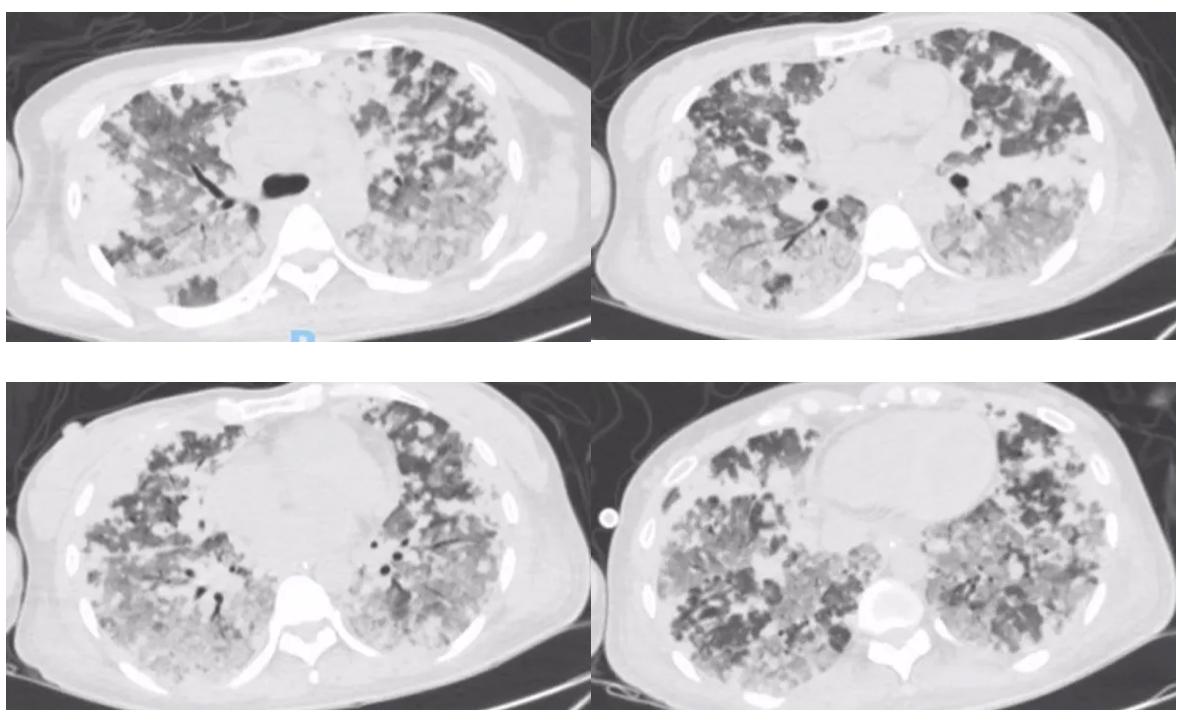

复查胸部CT:

黄国鑫主任(影像科)点评:

与前两次CT对比第三次胸部CT提示肺部病变继续进展,肺部多形性结节部分融合,肺部磨玻璃渗出较前进展,但所有叶间胸膜、小叶间隔、中轴间质都无明显改变,小叶间隔无结节样改变,最早胸部CT即尚无明显弥漫肺泡出血时的表现双肺结节呈血行分布,另呈不同阶段结节,除血行分布,可见胸膜结节,这种情况用小血管炎、肉芽肿性血管炎不好解释。随着病情进展,第二次胸部CT还有一个特点就是双肺结节呈中央致密、周围磨玻璃样渗出,当时考虑血管炎、感染性疾病如真菌、结核等,但血行播散肺结核一般呈三均匀:分布均匀、大小均匀、密度均匀,结合临床基本排除。影像方面肿瘤首先考虑转移瘤,不支持点为转移瘤一般表现边缘光滑,但该患者结节边缘模糊渗出,不是典型的转移瘤征象。但综合患者肺部病变血行分布、胸膜分布、进展迅速,需考虑肿瘤性病变肺内转移。结合病史注意有无其他部位原发肿瘤。另CTPA未见肺动脉充盈缺损。